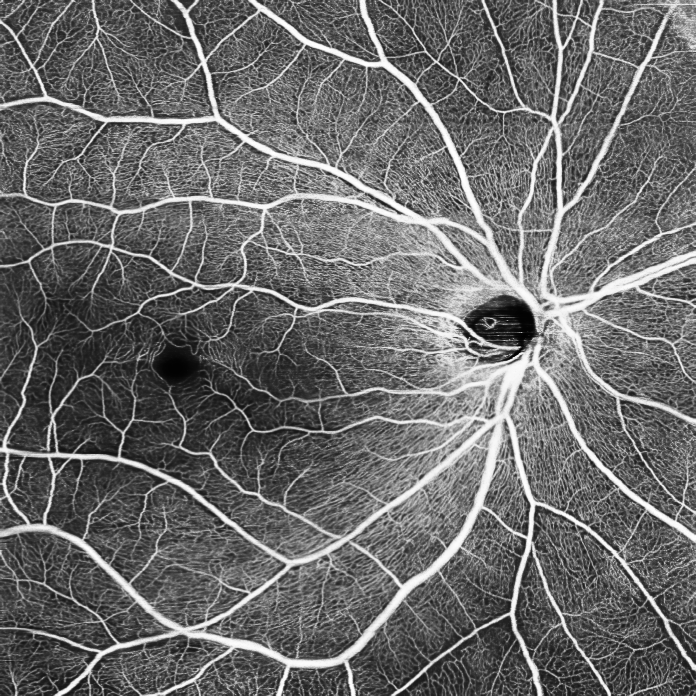

ОКТА зображення очного дна (рис.1)